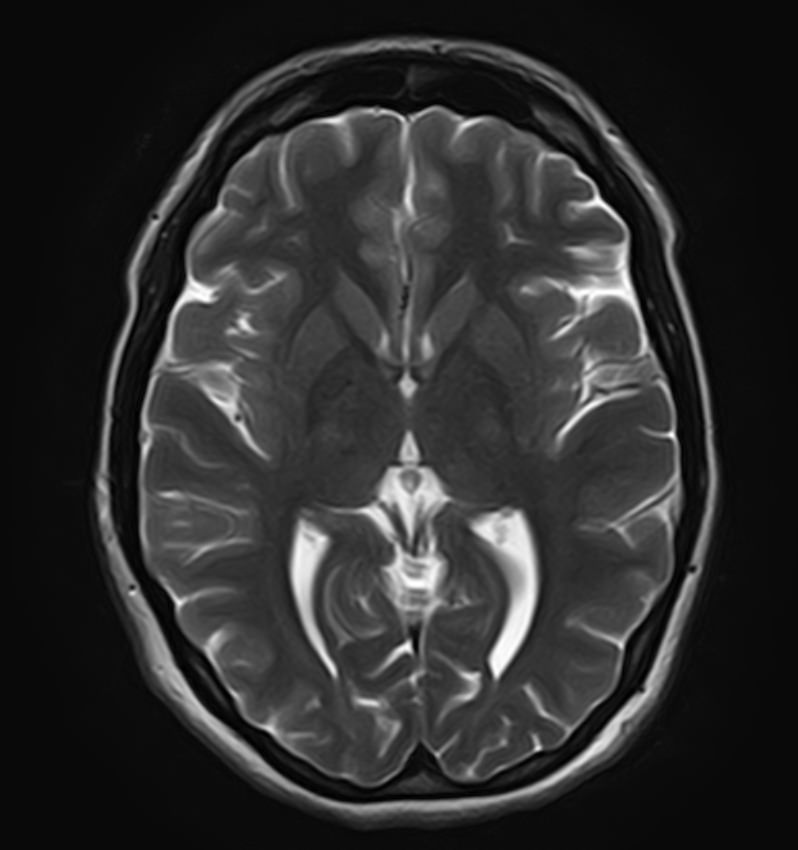

Сканирование проводится на современном высокопольном магнитно-резонансном томографе закрытого типа TOSHIBA VANTAGE TITAN 1,5 Тесла, который делает послойные срезы в разных плоскостях с шагом от 1 мм и на основе полученных данных создает трехмерные изображения превосходного качества. Метод исследования позволяет в мельчайших подробностях визуализировать состояние всех структур головного мозга и шейного отдела позвоночника, что дает возможность выявлять патологические изменения на ранних стадиях и назначать своевременное лечение.